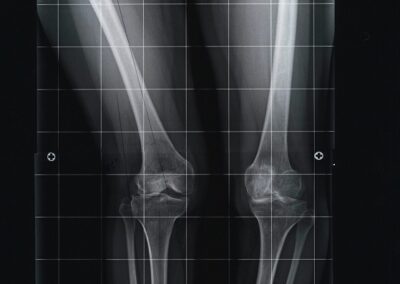

arthritis deformity surgery endoprosthesis hip prosthesis ilizarov ilizarov surgery infected nonunion knee prosthesis lengthening surgery limb lengthening surgery nonunion periprosthetic infection psodoartroz revision surgery total hip prosthesis total knee prosthesis